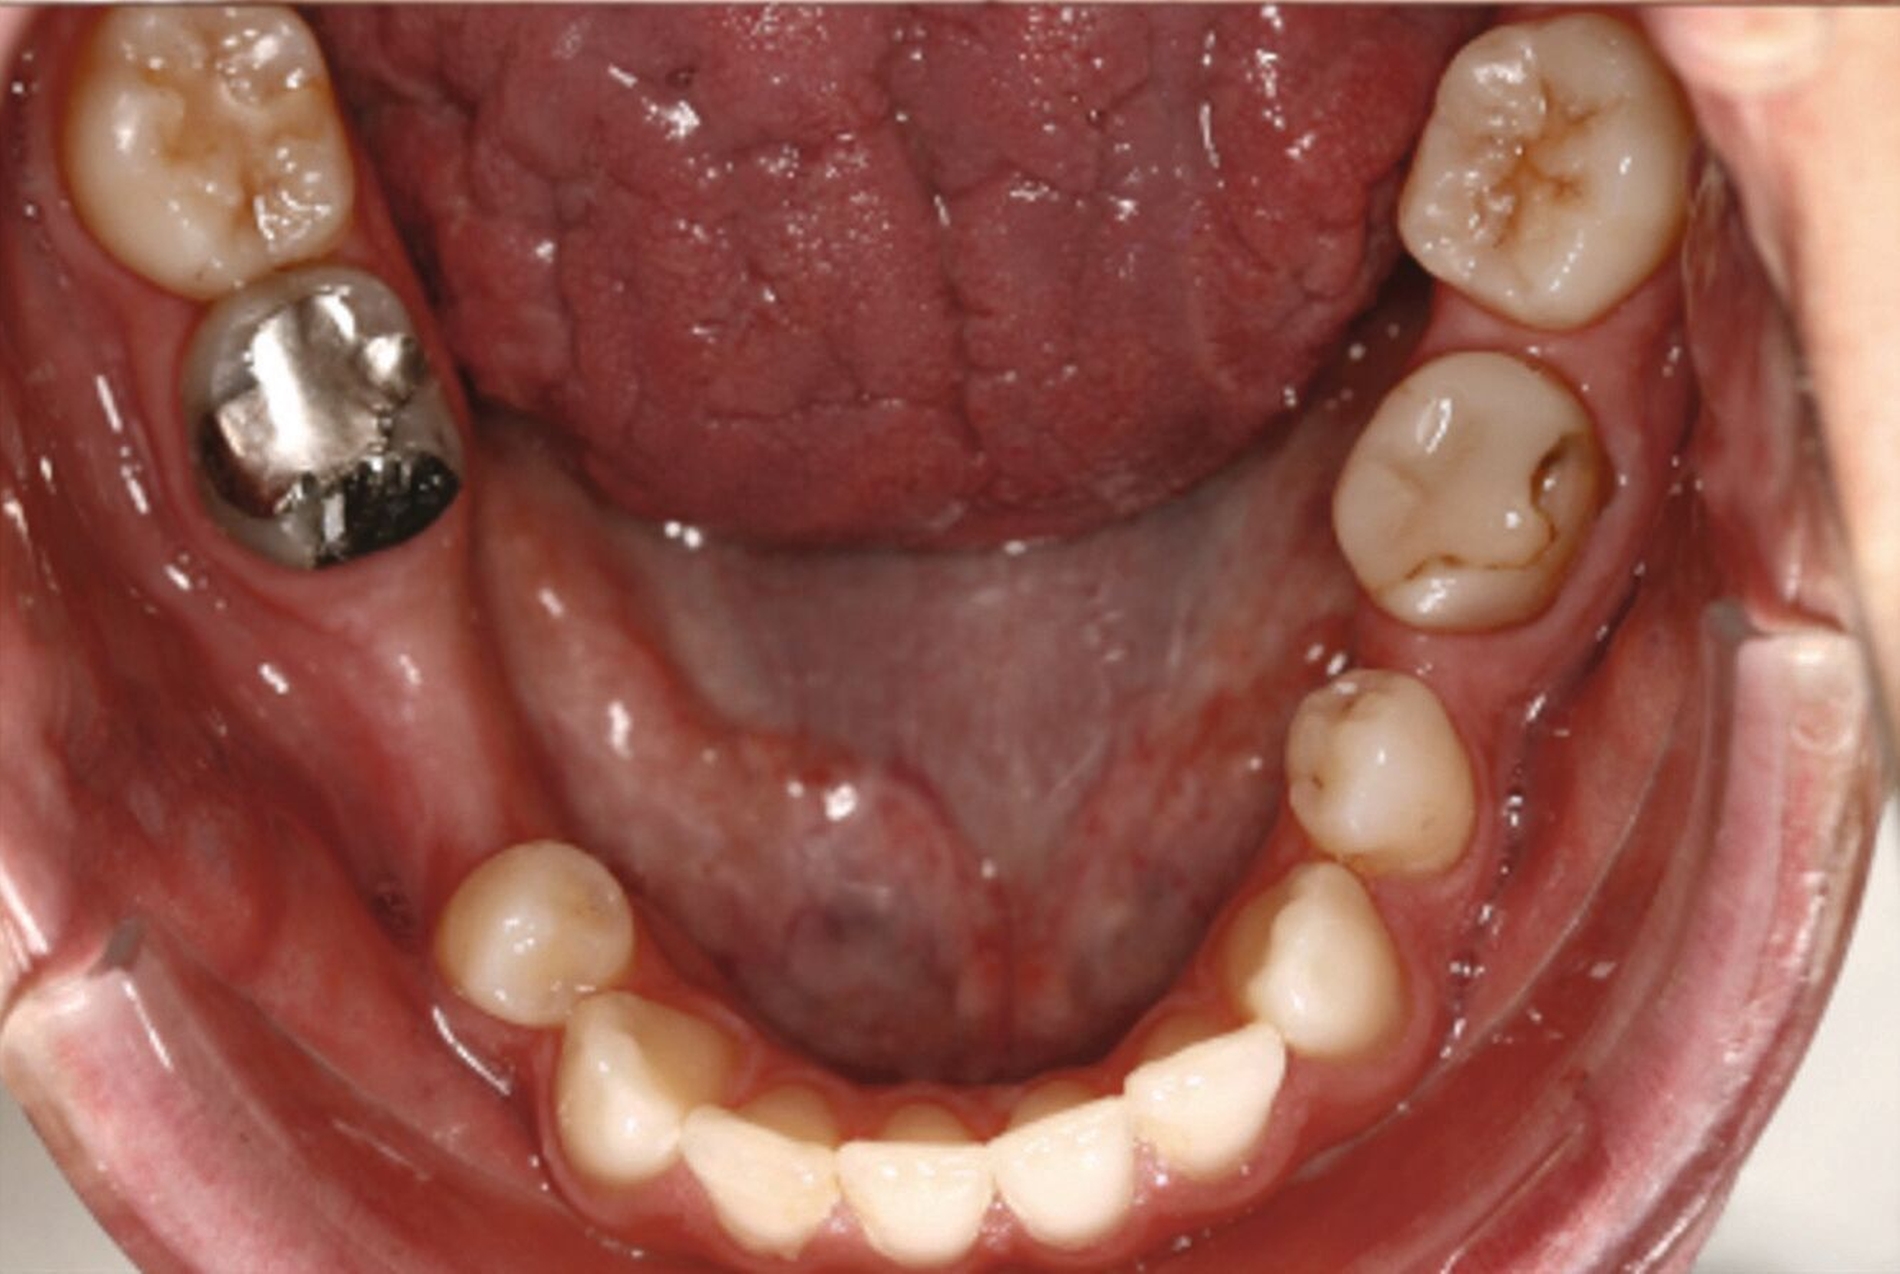

Ein 25-jähriger Patient stellte sich mit dem Wunsch nach Optimierung seines Erscheinungsbildes und seiner Kaufunktion in der kieferorthopädischen Praxis vor (Abbildung 1). Klinisch zeigten sich eine Angle-Klasse-III-Verzahnung mit einer 3/4 Prämolarenbreite Mesialokklusion beidseits und ein zirkulärer Kreuzbiss von 18–12/48–41 und 21–28/31–37. Es lagen ein negativer Overjet von -6,7 mm und ein Overbite von 5,1 mm vor. Eine Mittellinienverschiebung wurde sowohl im Oberkiefer – mit einer Abweichung von 4 mm nach rechts – als auch im Unterkiefer – mit einer Abweichung von 3 mm nach links – diagnostiziert (Abbildungen 2 und 3).

Aufgrund einer hohen Kariesanfälligkeit und einer klinisch floriden Parodontitis waren bereits mehrere Zähne des Patienten extrahiert worden, darunter 16, 11, 25, 38, 35, 45 und 46. Die mesiale Kippung und Aufwanderung der angrenzenden Zähne ließ vermuten, dass der Zahnverlust zeitlich weiter zurücklag. Aufgrund der reduzierten Langzeitprognose des Zahnes 11 entschieden wir uns gemeinsam mit dem Patienten für eine Ausgleichsextraktion des Frontzahns.